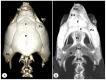

Anatomical Description of Loggerhead Turtle (Caretta caretta) and Green Iguana (Iguana iguana) Skull by Three-Dimensional Computed Tomography Reconstruction and Maximum Intensity Projection Images

The growing interest in reptiles has posed a challenge to veterinary clinicians due to the lack of a standardized system to perform anatomical studies similar to those used for dogs and cats. In this paper, we have attempted to describe, employing computed tomography and subsequent three-dimensional reconstructions, the normal anatomical features that comprise the skulls of two species of reptiles: the loggerhead turtle (Caretta caretta) and the green iguana (Iguana iguana). Computed tomography (CT) and subsequent image processing allowed the identification of the bony structures that comprise the head of these species. As a result, and based on previous articles, we propose the most significant anatomical differences and similarities between these species.